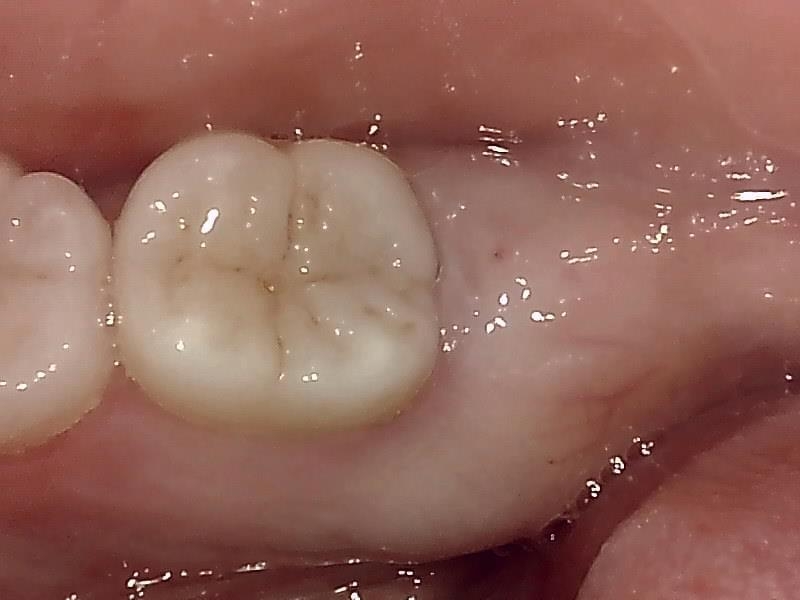

治癒

抜歯後、経過良好です。